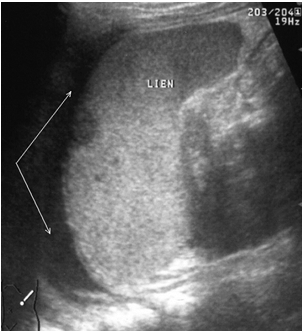

Фрагментация (отрыв полюса) селезенки представляет, по сути, частный вариант чрескапсульного разрыва с полным разобщением фрагментов органа. Наряду с раздельной визуализацией фрагментов выявляются линии разрывов и вышеописанные косвенные признаки, характерные для данного вида повреждений (рис. 10).

Рис. 10. Эхограмма полного поперечного разрыва селезенки. Линия разрыва указана стрелками.